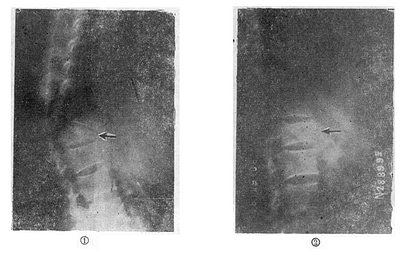

(三)爆裂型骨折的治疗 如不合并严重的神经系统症状,损伤又在两周以内者,可以用双Harrington法,撑开矫正,或用Dick手术;可以获得满意的结果(图73-13)。复位后需融合相邻两个椎间隙,因为CT常显示在爆裂型骨折中,相邻的上、下两个椎间盘均有损伤,如不融合,日后取棍后会出现腰痛。使用本法时,如前纵韧带完整,则很容易恢复椎体前方的高度。但爆裂型骨折存在下述三种情况时,需行前路减压术:①合并神经系统症状较重者;②就诊较晚,已两周以上者(常常10天以上就复位比较困难);③脊柱CT扫描显示已有较大的骨折片突出椎管内,使髓腔管变窄超过30%以上者,预示后纵韧带已有明显损伤,使用后路手术方法已无法使骨折片复位。Kostuik复习了日本和多伦多治疗脊柱骨折的结果后证实,前路减压术能使膀胱、肛门及肢体功能得到更好的恢复。

爆裂型骨折的治疗

图73-13 爆裂型骨折的治疗 ①术前,骨折脱位;②术后,侧位;③术后,正位